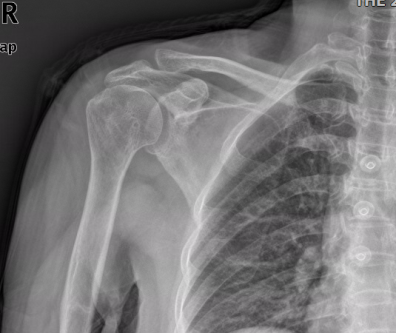

但庄阿姨一听要手术连连拒绝,又回去了。这一拖又是一年,今年3月份,庄阿姨肩关节长期疼痛难忍,甚至已严重影响日常生活,才再次找到薛主任。其术前X线片提示:“右肱骨头向上半脱位,右肩关节退行性病变”;术前MRI提示:“右肩巨大肩袖撕裂,冈上肌脂肪浸润,右肱骨头上移,关节腔积液”。